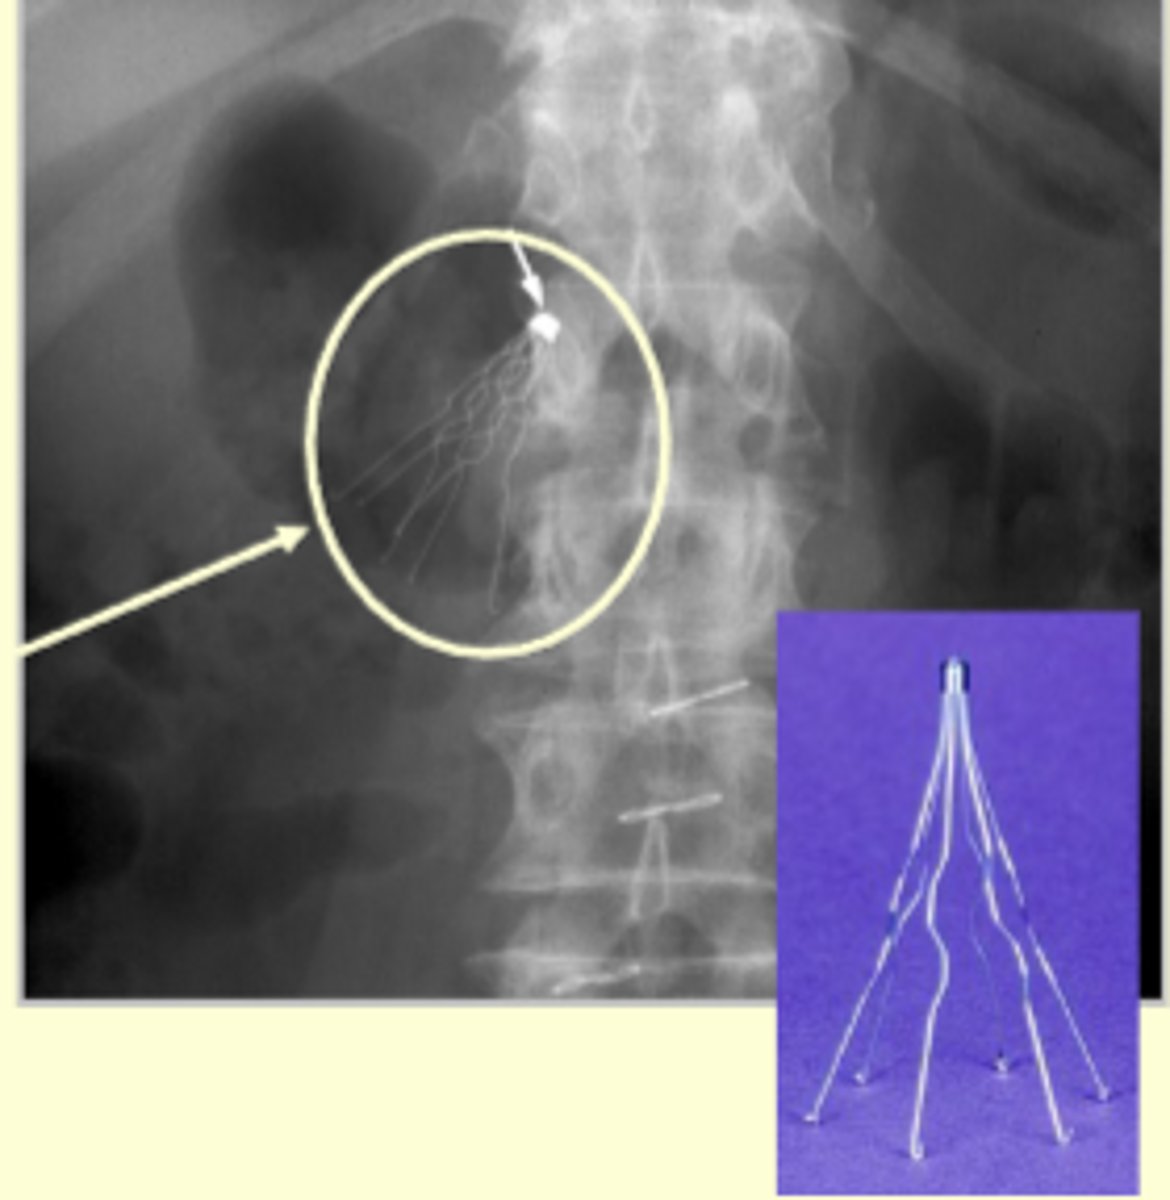

Balloon Angioplasty

What condition does balloon angioplasty primarily address?

Stenosis due to atherosclerosis (fatty deposits in the artery); alleviates stenosis and restores blood flow

How is balloon angioplasty performed?

A deflated catheter is threaded into the stenotic area, inflated to open the vessel, and then removed after deflation.

What is often placed in the vessel after balloon angioplasty to prevent closure?

A stent (a mesh tube)